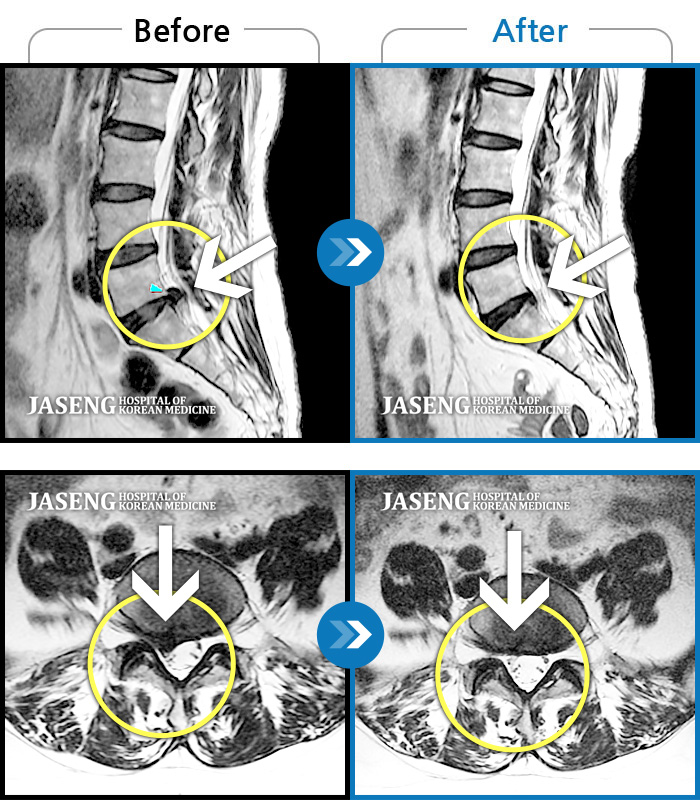

허리디스크

보라매 · 빈상은 원장

엉치에서 좌측 다리 뒤쪽으로 통증과 저림이 매우 심해요.

촬영시기

2024.06.08 ~ 2024.08.31

2024.12.24

조회수 410